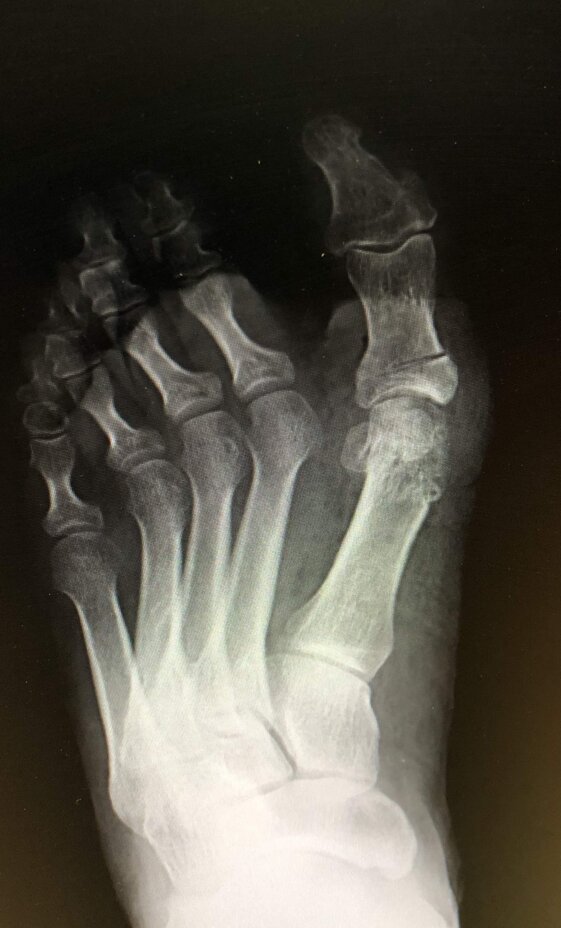

Radiografie post-operatorie in AP e LL di intervento di correzione di Alluce Valgo con tecnica mini-invasiva senza utilizzo di mezzi di sintesi metallici. Per l’osteotomia di correzione del I MT ho utilizzato un pin riassorbibile che quindi non è visulizzabile alle radiografie, mentre per l’osteotomia della prima falange del primo dito non ho utilizzato alcun mezzo di sintesi